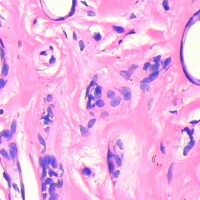

认为汗管瘤是由脂肪代谢障碍所引起的人体表皮小汗腺导管的一种痣样肿瘤,与内分泌、妊娠、月经及家族遗传等因素有关。切片显微镜下症征为真皮上部可见多数管埋入纤维基质中,导管内衬两层上皮细胞,腔内含有无定形碎片。部分导管为小的上皮细胞索构成逗点状或蝌蚪状外观。